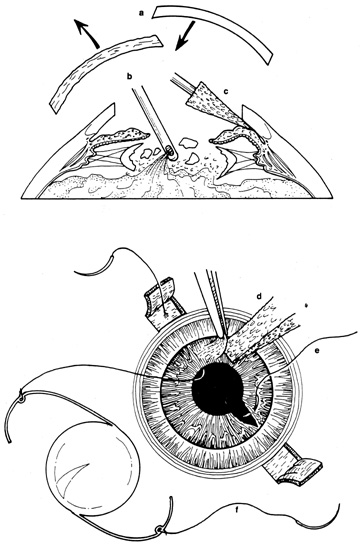

If the anterior chamber is formed and the wound is watertight, sutures may be placed directly without entering the anterior chamber with instrumentation. For a wound that is less stable, a viscoelastic may be irrigated into the anterior chamber either directly through the wound itself or through a separate limbal paracentesis incision (Fig. 4). This will aid in re-forming the anterior chamber, tamponade intraocular contents, and protect the corneal endothelium, iris, and lens. Balanced salt solution or air may also be used to re-form the anterior chamber. In most cases, a limbal paracentesis is preferred because it will minimize disruption of the wound edges and permit better access as the case proceeds.5 A 15-degree sharp microsurgical knife or MVR blade may be used to create the paracentesis, placing the incision 90 degrees away from the wound. If a very shallow or flat anterior chamber is present, extreme care should be taken to avoid damage to the iris or lens when constructing the paracentesis site.

Initially, the limbus should be reapproximated with 8-0 or 9-0 nonabsorbable nylon or silk sutures to restore normal anatomic relationships. Any prolapsed or incarcerated iris should be repositioned, after which the corneal portion of the laceration is repaired as described earlier. The scleral laceration is then explored to ascertain the extent of damage. For smaller lacerations, a localized conjunctival peritomy is made to explore the wound. A 360-degree peritomy is made for larger lacerations to explore all quadrants. During exploration, care is always taken to avoid iatrogenic avulsion of intraocular contents. The use of loupes rather than the surgical microscope may facilitate the broader three-dimensional view required for repair of scleral laceration.

There are many options in selecting suture material for scleral closure. Although some surgeons prefer nonabsorbable sutures (i.e., 8-0 nylon or silk), others may use absorbable materials (i.e., 7-0 polyglactin 910). For larger defects, nonabsorbable sutures should be used. When suturing gaping wounds, it may be helpful to advance the needle completely through one wound margin and then reload the needle holder before making a second pass, thus avoiding globe distortion (Fig. 17). For closing sclera over prolapsed uvea, the wound is often most easily closed from the anterior (limbal) end with interrupted sutures, which are placed successively, proceeding posteriorly. This is called the “zippering” or “close-as-you-go” technique. With this technique, sutures are placed in close proximity to one another in an attempt to achieve oversewing of the uveal tissue with the sclera. The surgical assistant may use a spatula to gently depress the uvea into the eye during suture tightening to avoid tissue incarceration during scleral closure (Fig. 18). Another suturing strategy is to successively bisect the wound while having the assistant use a spatula to press any prolapsed tissue back into the eye as sutures are tightened.